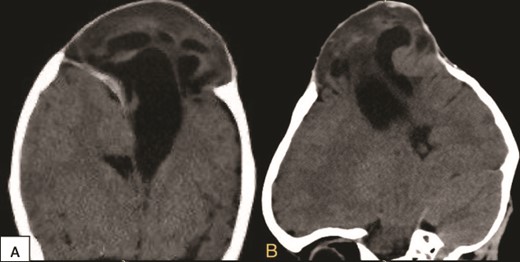

Upon seeking medical advice, the patient was found to have a left parietal pseudomeningocele and later he underwent a duraplasty with evacuation of the pseudomeningocele but months later, a bulge reappeared. Multiple follow ups were done through which CSF aspiration by needle was performed with the hope of CSF to stop spontaneously. At the age of 2 years, an external ventricular drain (EVD) was inserted without significant improvement and a complain of right arm and leg weakness was noticed, so he was referred to our hospital for further treatment. Hence, a CT scan was done (Fig. 2), revealing a median and left paramedian parietal encephalocele causing detorsion and compression of the sagittal sinus, and part of the primary motor area was extending into the encephalocele region.

Preoperative coronal (A) and sagittal (B) brain CT scan demonstrating the encephalocele.